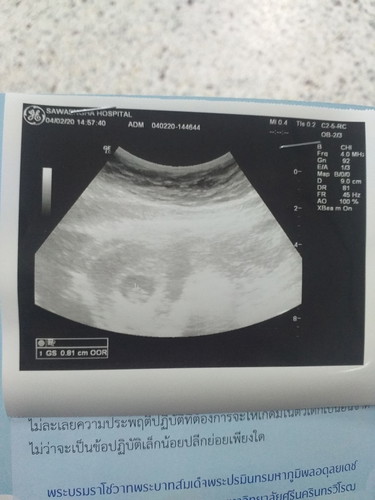

ไปฝากท้องตอน 7 w หมอไม่ได้แจ้งรายละเอียดอะไรมาก อยากทราบว่าซาวออกมาแบบนี้ เห็นตัวน้องไหมค่ะ ท้องแรกดูไม่เป็นค่ะ #กังวนเรื่องท้องลมด้วยค่ะ

ถ้าผิดปกติหมอจะแจ้งค่ะ คุณแม่น่าจะท้องสมบูรณ์มีถังตั้งครรภ์และตัวเด็กแล้วค่ะ

เหมือนจะเห็นเป็นก้อนๆค่ะแม่ คราวหน้าเตรียมคำถามก่อนไปพบหมอค่ะแม่

หมอก็ทำเครื่องหมายบวกตรงถุงตั้งครรภ์มีน้องอยู่ค่ะตัวเล็กๆ

เห็นน้องแล้วนะคะคุณแม่

เห็นคะ แต่ตัวจะเล็กมาก